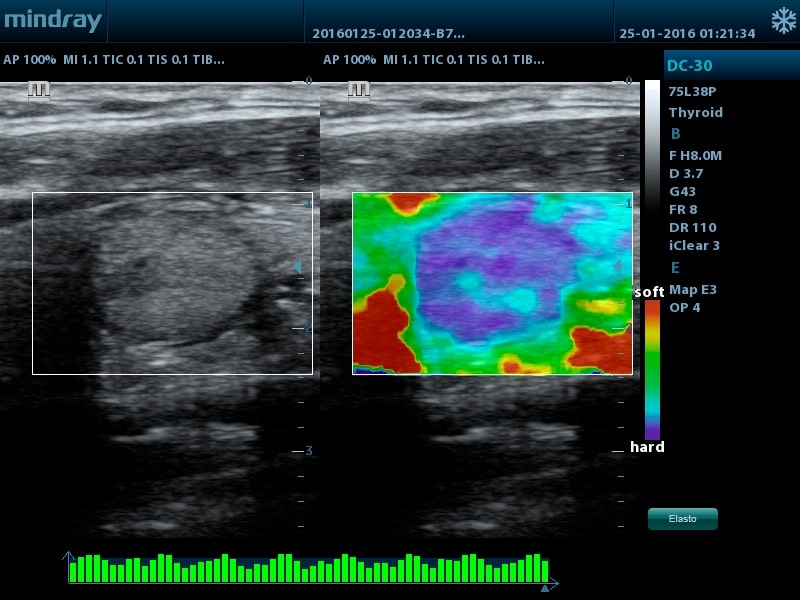

- Запатентованный компанией Миндрей метод эластографии для оценки эластичности ткани (поддерживается на датчике 75L38P)

- Линейный датчик 75L38P, 3,4-12,9 МГц, апертура 38 мм, 80 элементов